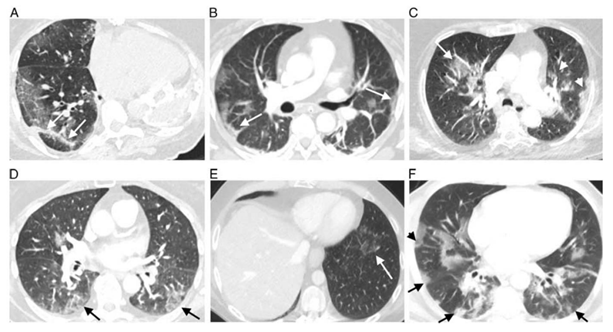

COVID-19影像学无特异性,典型的影像学表现是靠近肺边缘的多发的磨玻璃样结节,会有很多细小的肺动脉栓塞以及肺的缺血性坏死。不典型的患者可以在肺叶中出现晕轮征或反晕轮征。如下图,A、B、D、F为COVID-19典型影像学,双侧外侧野多发磨玻璃样结节;C、E为不典型影像学,由肺细小动脉栓塞导致晕轮征或反晕轮征。

图片

图片来源:J Thorac Imaging, 2020, 35(6):346-353.